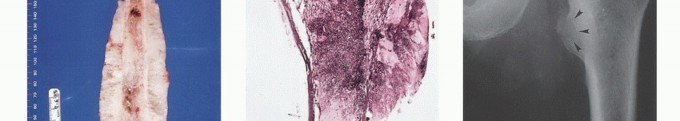

Imaging Set 1: Pathophysiology and Staging Fundamentals

- Plain Radiography: The cornerstone of initial evaluation. It accurately predicts the diagnosis in over 80% of extremity bone tumors. It defines the lesion's location, zone of transition (narrow/sclerotic = benign/slow; wide/permeative = malignant/aggressive), cortical destruction, and periosteal reactions (Codman triangle, onion-skinning, sunburst pattern).

- Computed Tomography (CT): The modality of choice for assessing fine osseous detail, cortical integrity, and matrix mineralization. Thin-slice (≤1 mm) helical CT allows for precise 3D reconstructions. Intravenous contrast is essential to delineate the relationship of the soft tissue mass to major vascular bundles. Chest CT is mandatory for staging to rule out pulmonary metastases.

- Magnetic Resonance Imaging (MRI): The gold standard for evaluating the local extent of the tumor. It accurately defines the intramedullary extent (allowing calculation of bone resection levels), soft tissue extension, joint involvement, and the presence of skip metastases. T1-weighted images best define marrow replacement; T2-weighted and STIR sequences highlight peritumoral edema and the soft tissue mass. Contrast enhancement differentiates cystic from solid components and clarifies neurovascular proximity.